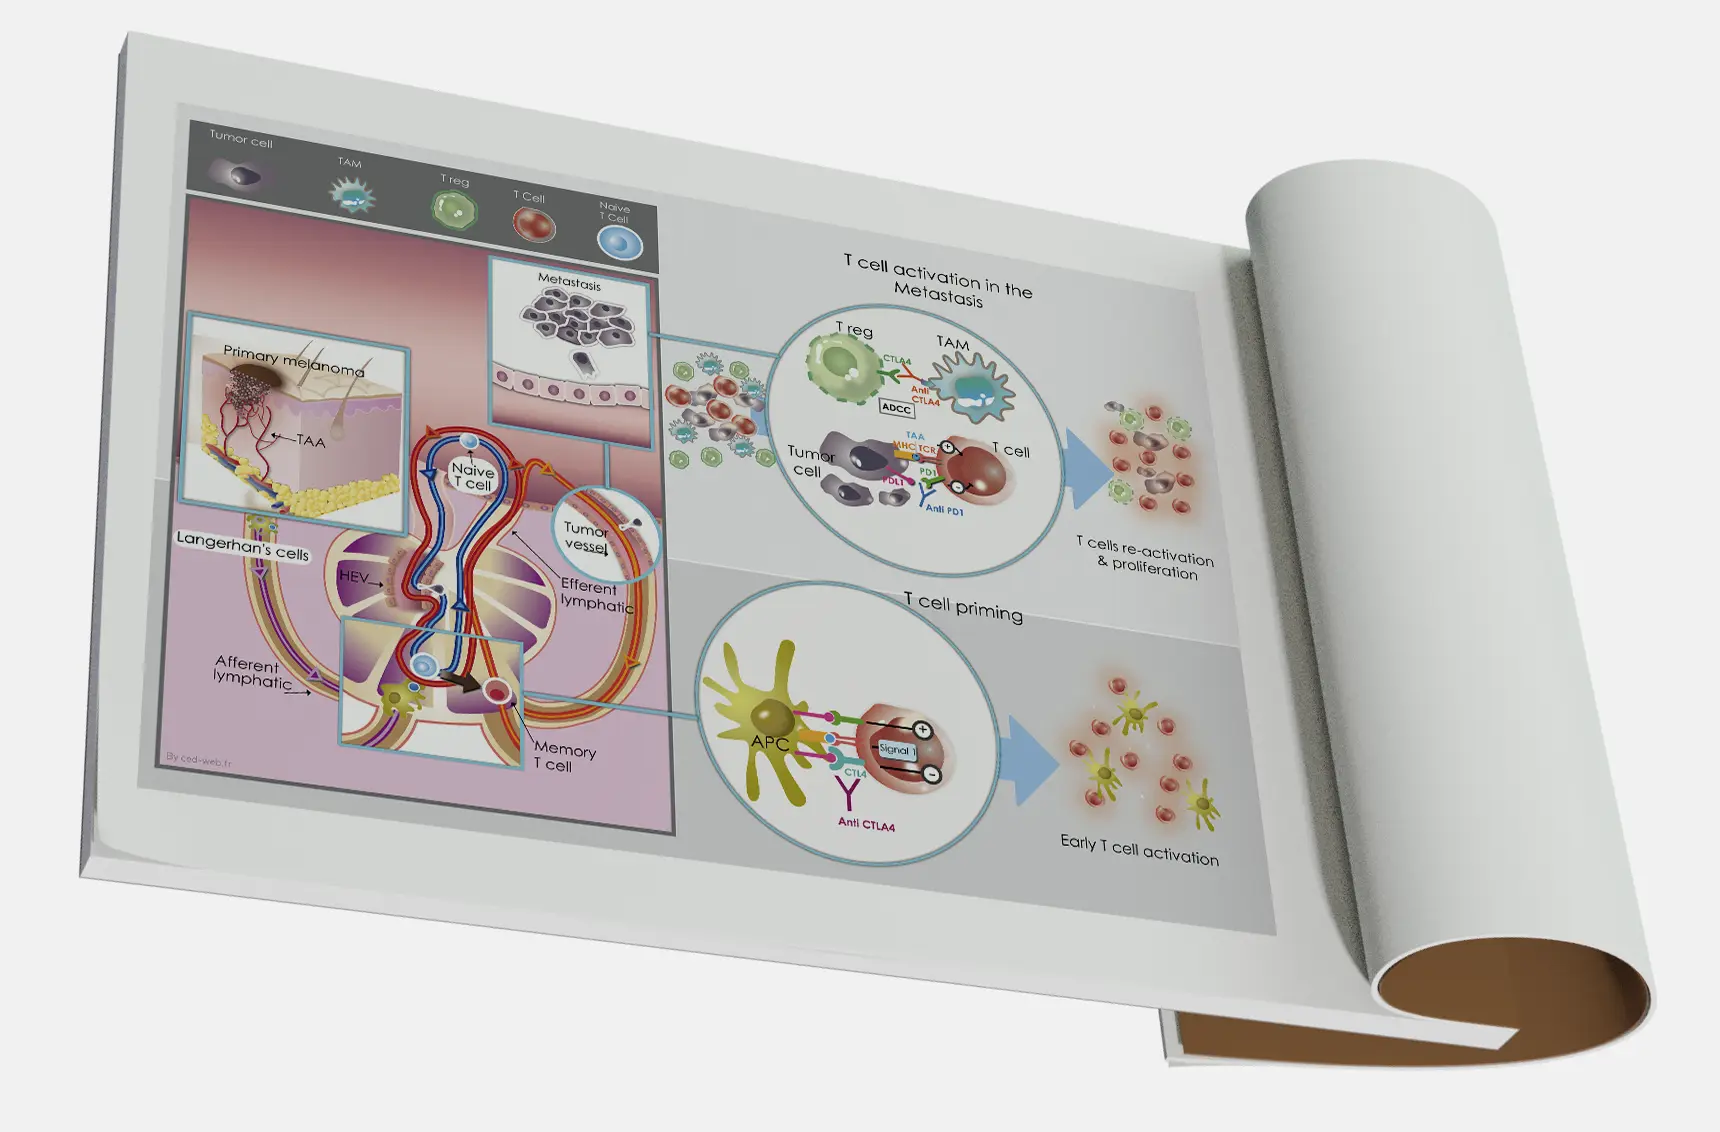

Découvrez notre collection unique d’illustrations conçues pour le domaine médical et scientifique. Chaque création combine rigueur scientifique et créativité artistique, offrant des visuels clairs et pédagogiques pour simplifier des concepts complexes.

De l’anatomie humaine aux processus biologiques, nos illustrations sont idéales pour enrichir des supports de communication, des publications académiques, des présentations professionnelles ou encore des formations en ligne.

Ce portfolio reflète notre passion pour la vulgarisation scientifique et notre engagement à transformer des connaissances spécialisées en outils accessibles et impactants.